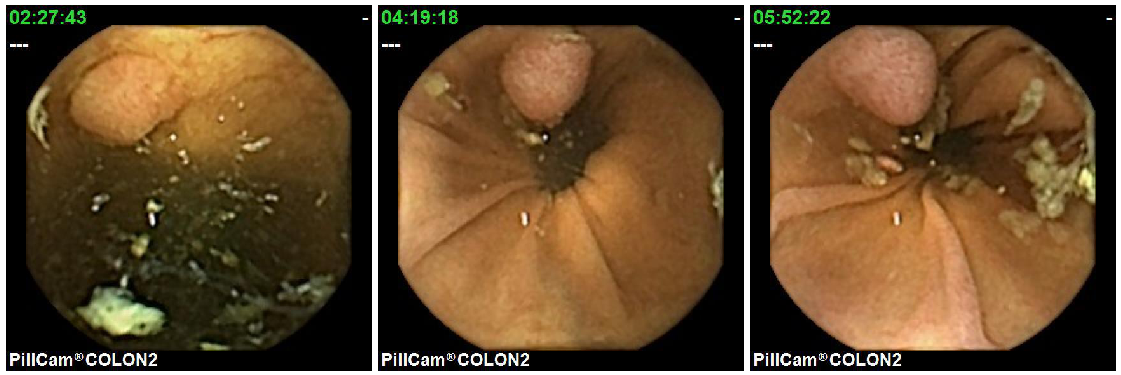

With regard to the specific goal of polyp detection, most of the published systems have been reported and validated as automatic detection methods. However, because of legal and practical reasons, these systems cannot be used for automatic diagnosis and can only be deployed as decision support systems which filter the whole set of frames to allocate physician’s attention to those images that show potential polyp structures. In most cases, this is a needle-in-haystack problem because of the occasional appearance of images with these pathologies. Figure 1 shows two sequences from different procedures where a polyp is observed. It is important to point out that, in both procedures, those are the only images of the whole procedure where a polyp is visible. Figure 2 shows some random images from the same procedures.

The second important point to consider when creating the database and its evaluation methodology, is that although all polyps have common visual characteristics, the appearance of different polyps from the same patient must be considered. The first row of Figure 5 shows three different polyps from the same patient, while the second row shows three polyps from different patients. As it can be observed, those polyps from the same patient are generally similar in shape and texture while the polyps from other patients are more diverse. It is for this reason, that training and test set must not use images from the same procedures.

Figure 6 shows 9 polyp samples of different sizes and morphologies.